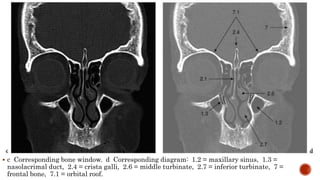

 c Corresponding bone window. d Corresponding diagram: 1.2 = maxillary sinus, 1.3 =

nasolacrimal duct, 2.4 = crista galli, 2.6 = middle turbinate, 2.7 = inferior turbinate, 7 =

frontal bone, 7.1 = orbital roof.